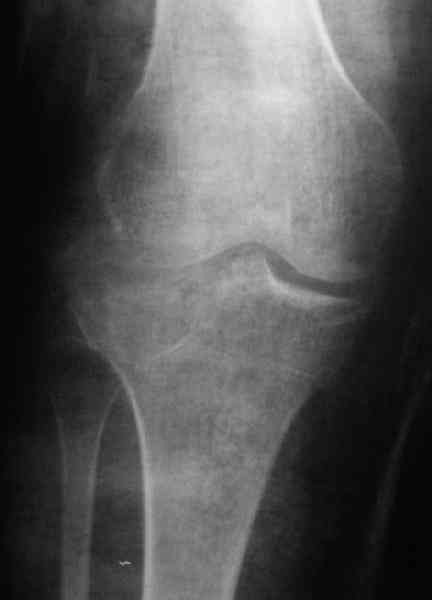

Застарелый перелом 41С3

Обратился больной 46л. 3-месяца назад в каком-то городке Дальнего Востока упал с высоты, сделана Р-графия, наложена гипсовая повязка, от предложенной операции отказался и уехал домой, дальше где и как лечился, не говорит.

Ходит при помощи двух костылей, жалобы на боли при нагрузке, в покое и при движении, без нагрузке боли нет, разгибание 175 гр, сгибание 90 гр, симптомов повреждения связочного аппарата к/с не определяется, от предложенного артродеза пока отказывается.

По тактике лечения, более импонирует второй вариант, но наружная плато расколота и туда при нагрузке внедряется н/мышелка бедра, поэтому после дистракции как репонирвать: или стяжными винтами, или изогнутами спицами или субхондральная костная пластика?

У пациента основной проблемой является импрессионый перелом наружного мыщелка, уже неправильно сросшийся, по-видимому. Аппаратом закрыто можно только подправить угол на уровне метадиафиза. Что

улучшит разве что внешний вид конечности, но не решит основной проблемы - грубой деформации суставной поверхности.